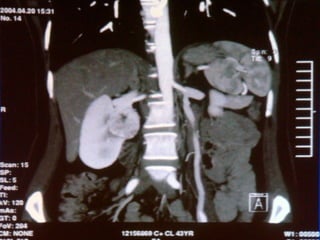

NEFRECTOMIA VLP  GRANDES RINS POLICISTICOS Premal J. Desai, et al. BJU, vol 101, numero 8, 1009-1023, 2008